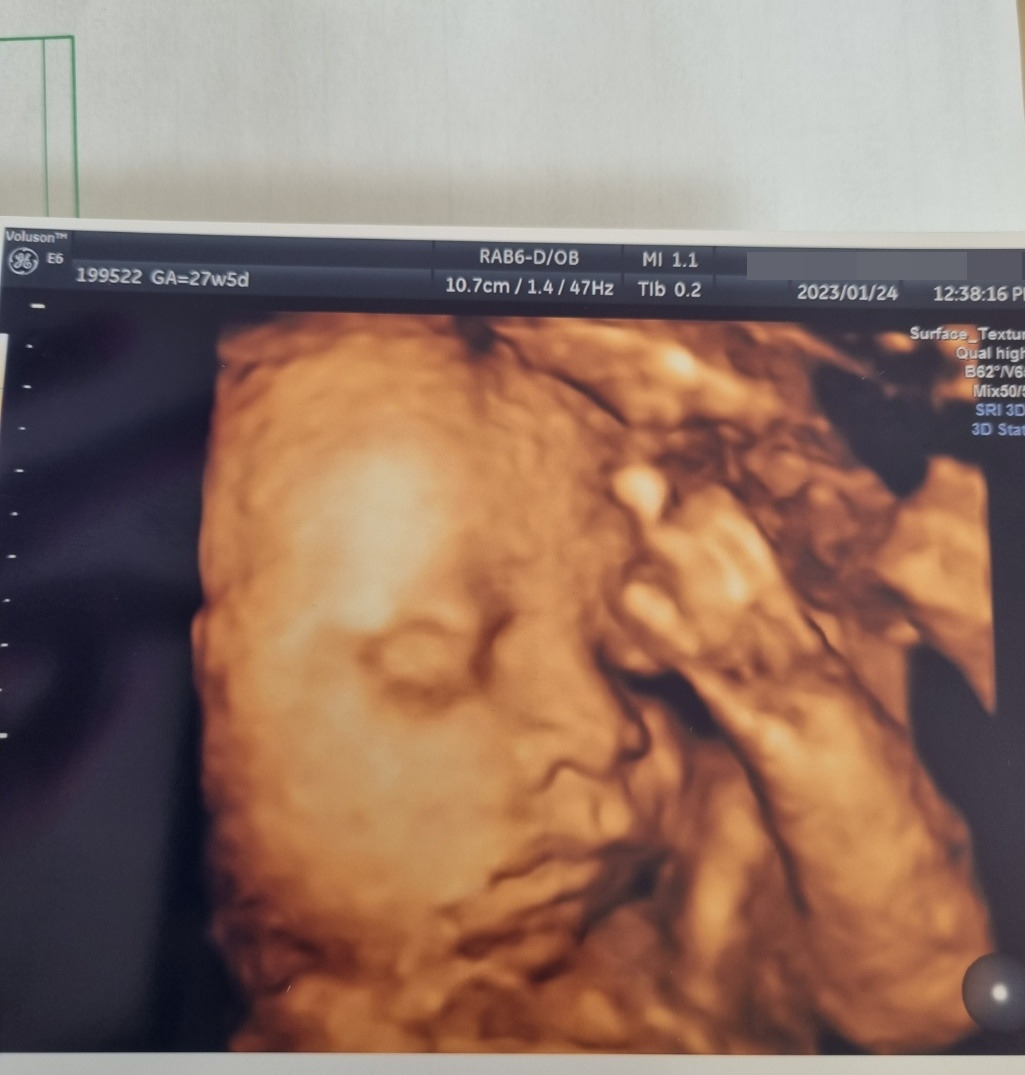

출산까지 마음이 편안한 적은 없었다. 원체도 돌다리 두들기는 성정인데 이전 일도 있어서 더 불안했다. 반짝이는 아기 심장을 확인했지만, 매 순간, 매 단계가 잘 되고 있는지 확인할 방법이 없으니까, 산부인과에서 오라고 하든 오지 말라고 하든 주야장천 일주일에 한 번씩 검진을 갔었다. 그러다 피도 비쳐서 한 달 동안 병가도 내고. 10년 넘게 직장 생활하면서 미련퉁이인 건지 건강한 건지 병가 한 번 낸 적이 없었는데, 아기와 관련된 이슈로 한 번은 호르몬 주사 부작용으로, 이번이 두 번째였다. 전적이 있었기 때문에 병원에서도 한 달 진단서를 길게 끊어주셨고, 직장에서 큰 건 2개를 집에서 해결하기는 했지만 대체로 집에서 쉴 수 있었다.

비눗방울이 뱃속에서 뽀글뽀글 올라오는 느낌, 태동이라는 걸 하고 나서는 조금 안심했다. 적어도 내 뱃속에서 아이가 안온하게 놀고 있구나, 잘 지내고 있구나, 엄마한테 인사하는구나 싶어서. 임신 후기에 아기 태동이 심해지면 배가 아프다는데, 나는 그 배당김도 좋았다. 아이와 온전히 연결되는 느낌, 그래야 비로소 잠이 들었던 날들이다.

출산 2달 반을 앞두고 한 달을 병원에서 살았다. 아래가 영 뻐근한 느낌이 들더니, 조산기란다. 그것도 내가 병원 가자고 한 게 아니라, 내가 힘들어하는 걸 보던 남편이 가보자고 채근한 덕분이었다. 내 몸도 내 몸인데, 아기 상태에 너무 민감하지 않았구나. 아직 10주나 남았는데, 벌써 나오면 안 되는데. 인큐베이터에서의 7일이 엄마 뱃속에서의 1일과 같다는 간호사님의 말을 완전 신조처럼 새기고, 그때부터는 내 건강이고 뭐고 그냥 누워있었다.